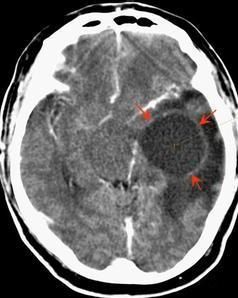

惡性腦膜瘤在CT的表現為腫瘤形態不規則呈分葉狀,可出現蘑菇征邊界不清、包膜不完整信號不均勻周圍水腫明顯,沒有鈣化。增強後腫瘤不均勻強化。腫瘤易侵犯腦組織和顱骨MRI的T1和T2像惡性腦膜瘤都為高信號。有時頸內動脈向腫瘤供血比較明顯。